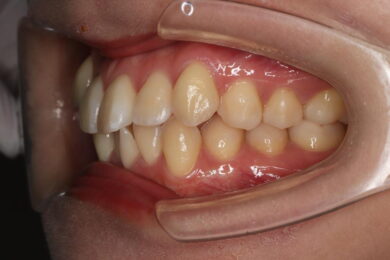

八重歯・叢生 マウスピース矯正(インビザライン)26歳女性 非抜歯

「前歯のガタガタ(叢生)と八重歯を治したい」を主訴に来院された患者様です。上下の歯にIPRを加え、歯列弓の拡大を行い、非抜歯で前歯のガタガタを整えました。顎間ゴムを用い、咬み合わせも改善されています。アライナーの装着時間が長く、チューイをしっかり使用していただけたため、非常に短時間で仕上がりました。

• 治療後